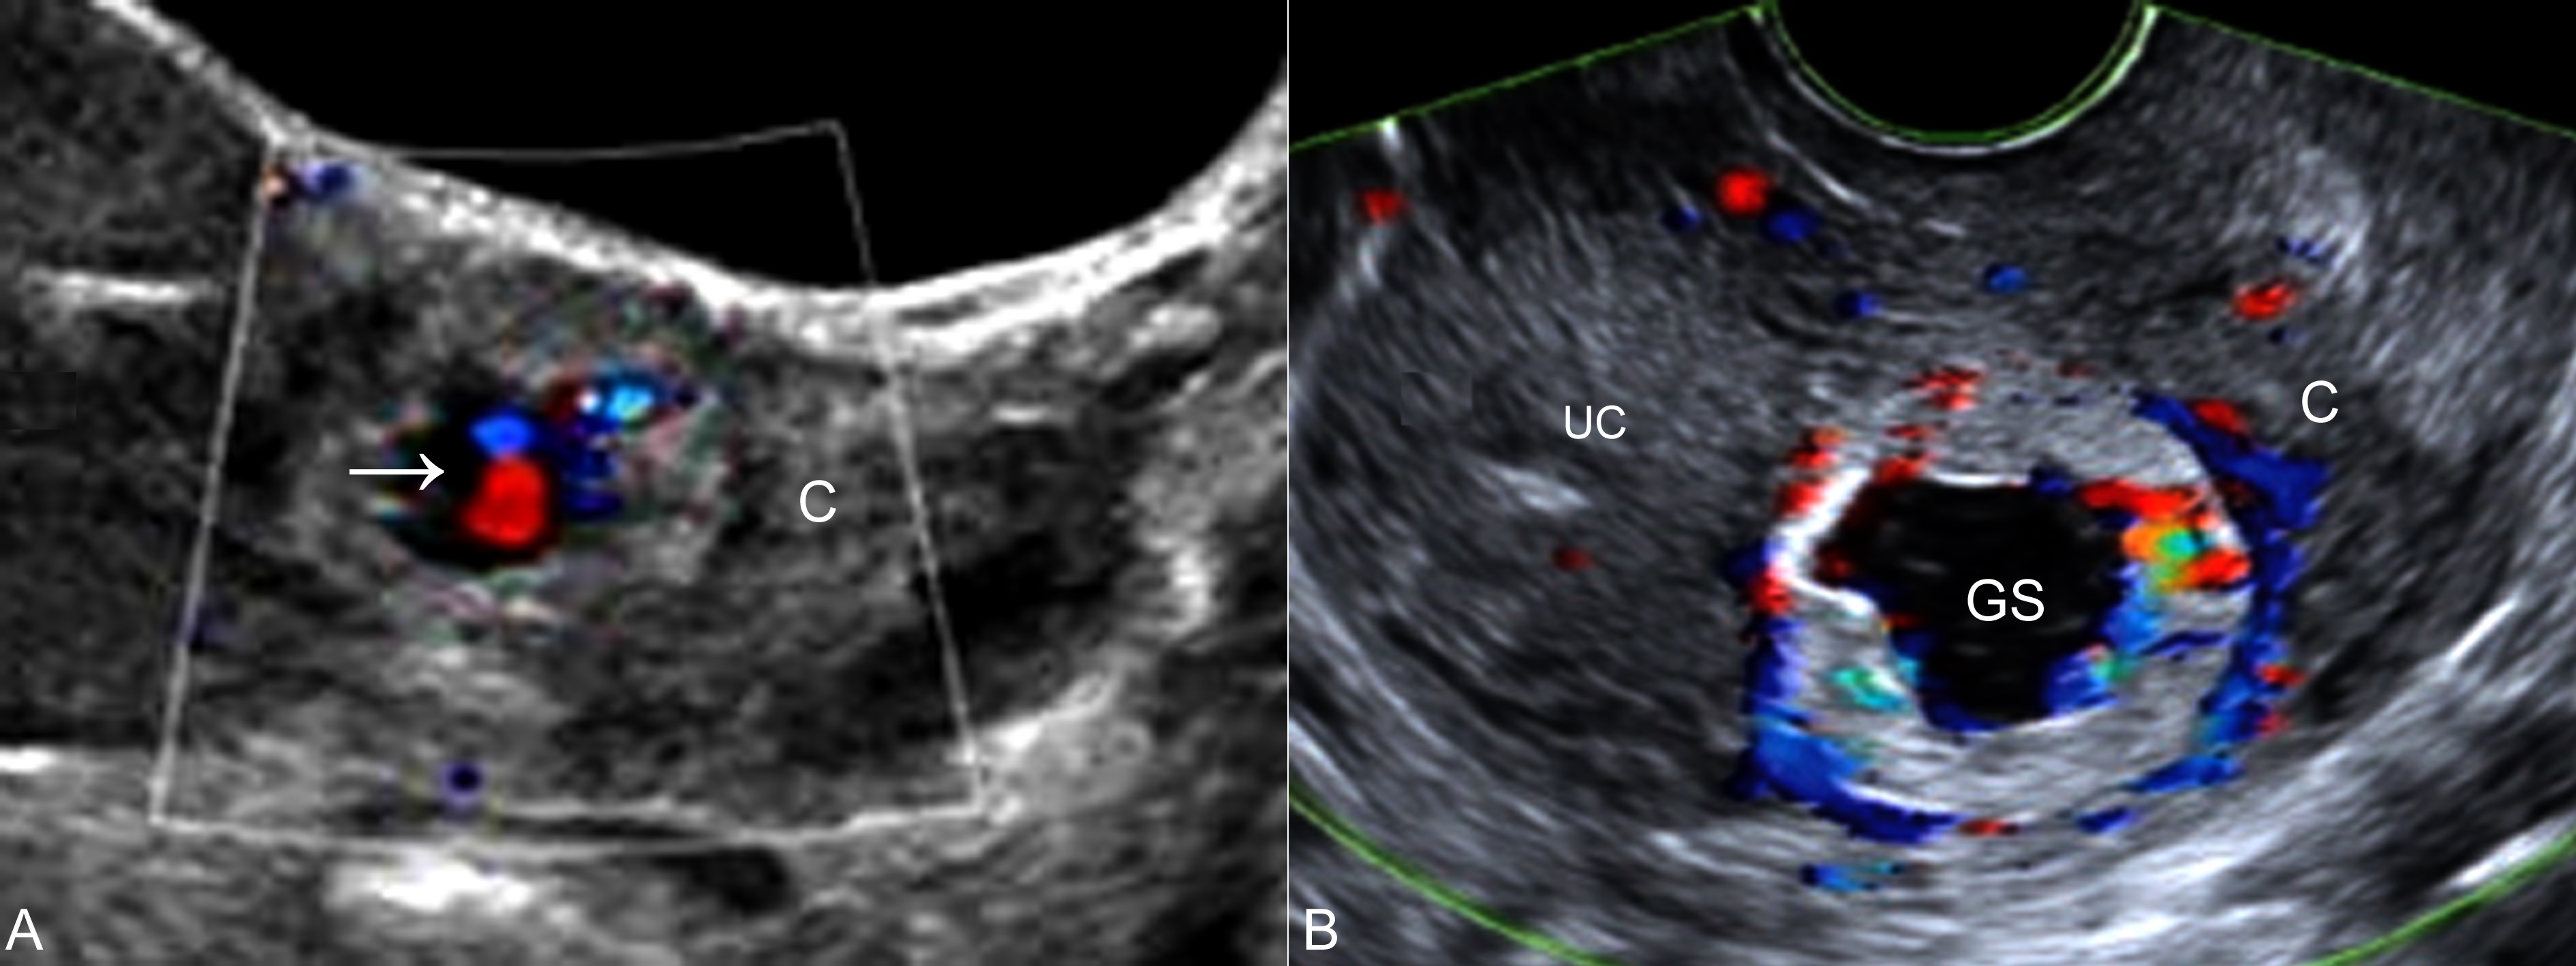

图1肌壁间妊娠声像图

A:TAU,子宫颈部(C)显示孕囊回声,CDFI检查内部可见胚胎血流(箭头)

B:TVU,宫腔(UC)处未见妊娠征象,宫颈部(C)孕囊(GS)周围显示血流增多